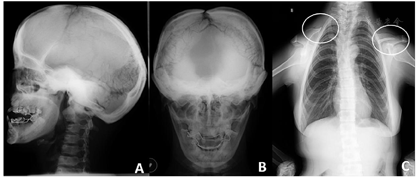

,反覆盖10mm,双侧尖牙及磨牙近中关系;51、61扭转,上颌牙弓狭窄,腭盖高拱,31、41间可见间隙约5mm(图2)。(3)影像学检查:①曲面断层片示多数乳牙滞留,恒牙迟萌,多颗埋伏阻生多生牙。54、64远中邻面低密度影及髓,牙根吸收(图3);②CBCT示全口恒牙排列紊乱,上下颌骨内可见13颗多生牙,均位于恒牙胚舌腭侧,形态类似相邻恒牙胚(图4);③头颅侧位片示头颅侧位片示上颌骨发育不足(NA-Apo:-5.9°),下颌前突(SNB: 98.2°;FH-NPo:90.0°),骨性III类错

畸形(ANB:-5.1°;FMA:31.0°)(图5)(表1);④头颅正位片示颅缝轻微增宽;⑤胸片示双侧锁骨远心端发育不足(图6)。